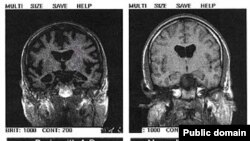

В настоящее время, клинический диагноз болезни Альцгеймера ставится путем исключения других причин потери памяти и снижения интеллекта: если у человека нет инсульта, опухоли мозга или тяжелой формы алкоголизма, а память ухудшается и слабоумие прогрессирует – значит у пациента болезнь Альцгеймера. Несмотря на использование данных компьютерной и магнитно-резонансной томографии, электоэнцефалографического и биохимического исследований клинический диагноз не является совершенно точным, и окончательный диагноз устанавливается после вскрытия мозга уже после смерти пациента.